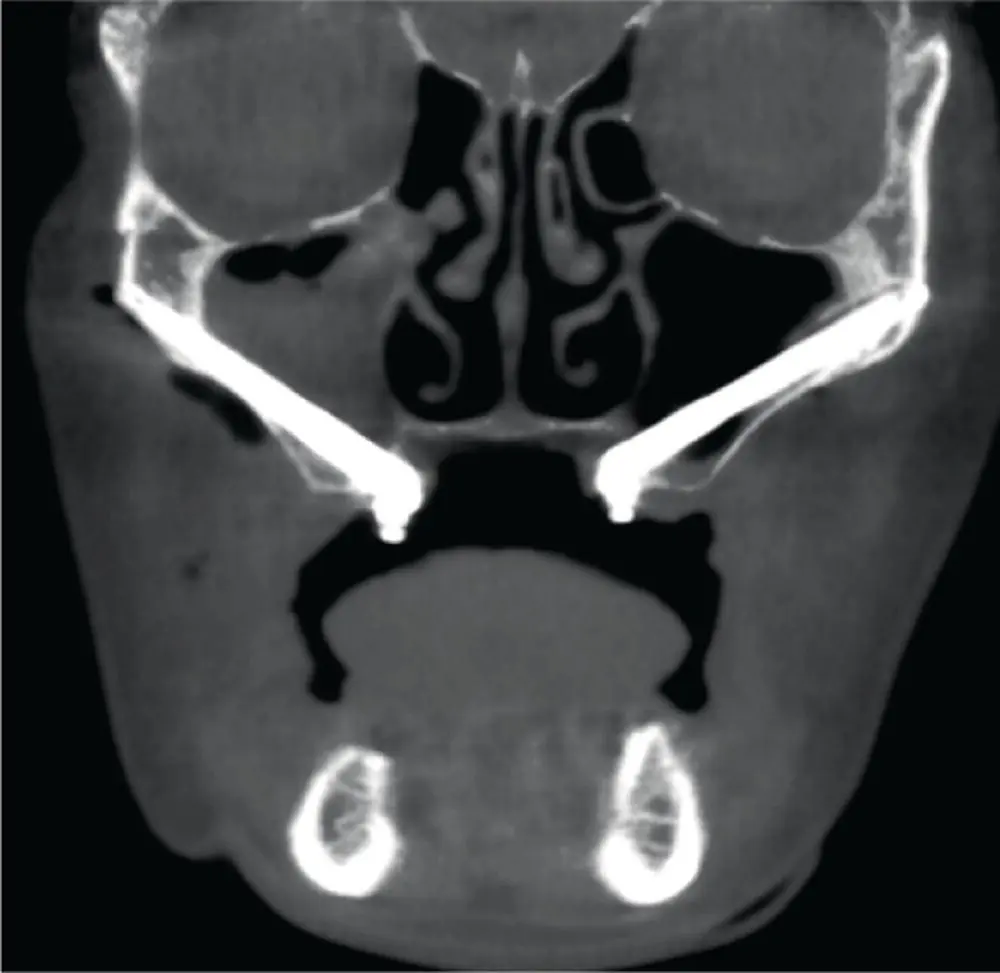

The use of zygomatic implants is becoming increasingly popular among surgeons for maxillary reconstruction in patients with pneumatization of the maxillary sinus and severe maxillary atrophy, and also for patients who have a significant maxillary defect following tumor removal or trauma. Zygomatic implants utilize the existing native bone of the posterior maxilla and zygomatic buttress and zygoma to stabilize long (>30 mm) implants without the need for bone grafting. There are several advantages to the use of zygomatic implants, including substantial reduction in overall treatment time, reduced costs, and decreased morbidity without the need for bone harvesting from a second surgical site. However, the use of zygomatic implants is not without possible complications. In a systematic review [43], the following complications were noted: sinusitis, non‐osseointegrated implants, infection, oroantral fistula, paresthesia of infraorbital and zygomaticofacial nerves, penetration of the orbital cavity, and labial laceration. Sinusitis and failure of osseointegration of the zygomatic implant are found to be more frequent than the other complications. According to the literature, the incidence of maxillary sinusitis after placement of zygomatic implants is 0–26.6% ( Figure 3.22). It has been documented that the varied range results from different criteria used to classify the signs and symptoms of rhinosinusitis. A retrospective cohort study [44] was done to assess the relationship between zygomatic implants and maxillary sinusitis and showed a statistical increase in postoperative radiographic evidence of rhinosinusitis compared with the preoperative status of the sinus. Further analysis revealed increased signs of radiographic alterations of the maxillary sinus in patients who underwent zygomatic placement by an “intrasinus” versus “extrasinus” technique. However, from a clinical standpoint there was no statistical difference in symptoms pre‐ and postoperatively. Although studies have not found a cause‐and‐effect relationship between rhinosinusitis complications and zygomatic implant placement [45], in order to minimize the risk of maxillary sinus complications, surgical techniques that help preserve the integrity of the Schneiderian membrane should be employed [44]. A retrospective study [46] of 352 completely edentulous patients using 747 zygomatic implants using an extra‐maxillary technique found a 7% incidence of maxillary sinus infection ( n = 26). However, 21 of 26 patients with maxillary sinus infection had a history of sinusitis prior to placement of zygomatic implants. This complication was treated with antibiotics and nonsurgical treatment in seven patients, nonsurgical removal of deposits from the implant surface and irrigation with chlorhexidine in eight patients, and functional endoscopic sinus surgery was required in five patients. Some authors have also recommended the use of maxillary antrostomy to reduce the incidence of postoperative maxillary sinusitis [46].

Fig. 3.22. Right maxillary sinusitis associated with right zygomatic implant.